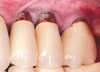

Fig 2. Radiograph suggested moderate bone loss around the implants.

Figure 2